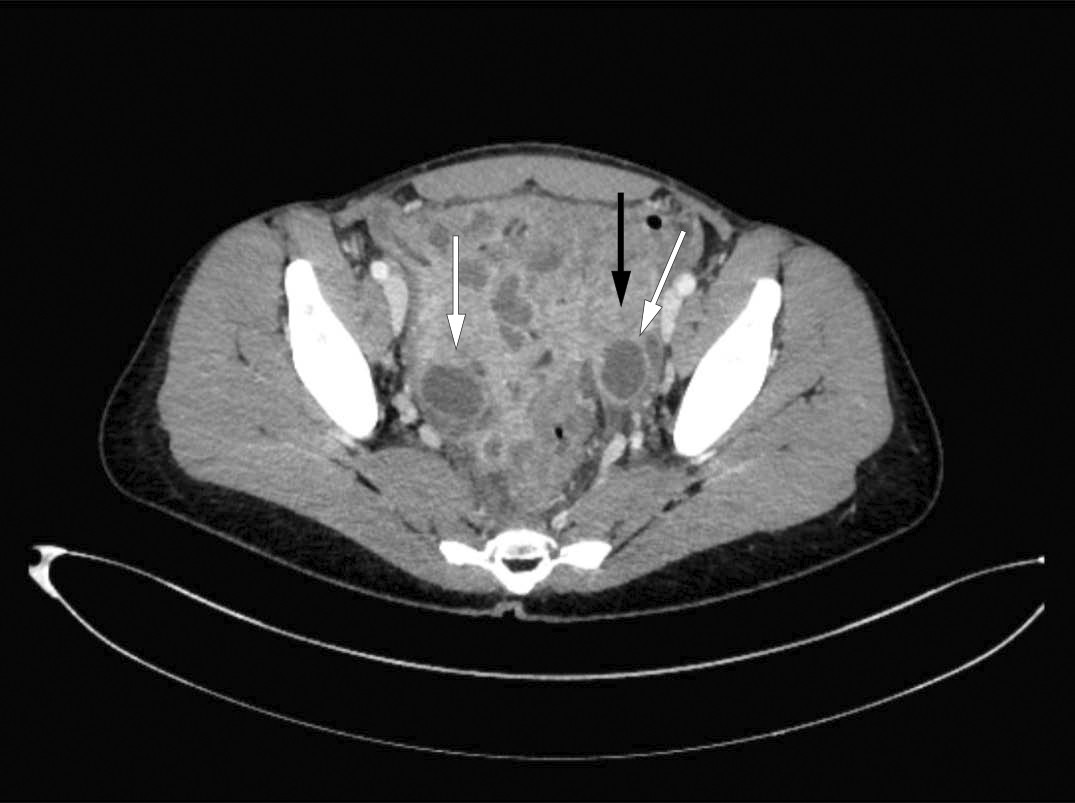

Pasienten ble innlagt for fjerde gang i løpet av fire uker, med økende magesmerter, medtatthet, infeksjonspreg og organpåvirkning. Dette var tolv måneder etter symptomstart. Hun hadde høy respirasjonsfrekvens på 24 pust/min, feber på 38,5 °C, takykardi på 100 slag/min og blodtrykk på 106/64 mm Hg. Ved undersøkelse var hun svært palpasjons- og slippøm i nedre del av abdomen. Blodprøver viste leukocytose på 17,9 ⋅ 109/L med overvekt av nøytrofile granulocytter på 15,6 ⋅ 109/L (1,7–8,2 ⋅ 109/L), høy CRP på 200 mg/L og forhøyede galleparametre med S-ALP (alkalisk fosfatase) på 178 U/L (35–105 U/L) og S-GT (gamma-glutamyltransferase) på 159 U/L (10–45 U/L). Det ble startet antibiotikabehandling med piperacillin og tazobaktam grunnet mistanke om intraabdominal abscess. Gastroenterolog foretok ultralydundersøkelse av abdomen, spesielt med fokus på tarm og bekkenområdet, og påviste forandringer i begge adneks og fortykket tarmvegg i colon sigmoideum. CT av abdomen, som inkluderte det lille bekkenet, viste bilaterale ovarialabscesser (figur 1). Blodkultur og urinkultur tatt ved innleggelse var uten oppvekst. Det var negativ serologisk prøve for hepatitt A, B og C, hiv og syfilis. Tuberkulosetesten Quantiferon-TB-Gold var negativ.